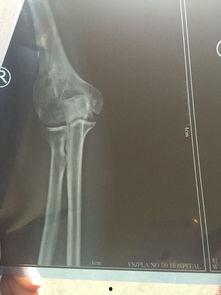

胳膊肘骨折了,这可真是个让人头疼的小麻烦。不过别担心,今天我就要给你带来一份超级详细的胳膊肘骨折康复训练正确视频攻略,让你在家也能轻松恢复,重拾活力!

胳膊肘骨折可不是闹着玩的,恢复得慢了,不仅会影响日常生活,还可能留下后遗症。所以,正确的康复训练至关重要。下面,我们就来看看有哪些训练方法吧!